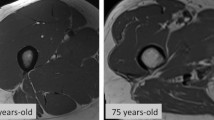

Data acquisition is achieved through the generation of a magnetic field that directs the alignment of hydrogen nuclei. The presence of gradient coils creates a smaller identification field, known as gradient field. The presence of the external gravitational field in combination with the gradient field produces a net external magnetic field. The resulting radio frequency coil provides the force necessary to rotate nuclear spins away from the direction of the external magnetic field. As the nuclear spins process back towards the direction of the external magnetic field, they emit radio frequency signals (i.e., T1 and T2), which are combined to form an image. The differentiation of the various tissues and organs is based on their specific magnetic resonance properties, such as the density of hydrogen atoms and relaxation time. For the study of body composition, variations in the radio frequency pulse sequence are used to make determinations about adipose tissue and fat-free mass. For example, a short T1 and a long T2 proton relaxation time are indicative of adipose tissue [4]. Notably, MRI scans provide information on muscle quality through the assessment of intermuscular and intramyocellular lipid depots via magnetic resonance spectroscopy analysis [5, 6]. MRI may also be used for the noninvasive estimation of fiber type composition [7].

Although MRI does not involve radiation exposure and has excellent accuracy in measuring quantitative and qualitative parameters of skeletal muscle, its high costs, technical difficulties and space requirement limit availability to well-equipped clinical and research centers. The time needed for the acquisition of high-quality scans and post-acquisition processing further impedes the large-scale implementation of MRI. Finally, the existence of multiple protocols for data acquisition impacts the standardization of this technique for the study of muscle mass and quality. Indeed, while most protocols focus at the mid-thigh level [8], others are based on the acquisition of single abdominal images that are subsequently used to estimate whole-body muscle and adipose tissue [9]. Bearing all these considerations in mind, MRI is presently better suited to small-scale research studies in which accurate measurements of muscle quantity and quality are needed.